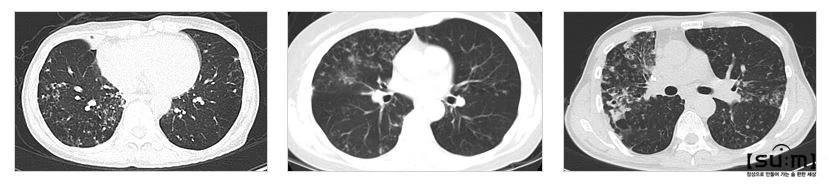

0.JPG 비결핵항산균에 의해 파괴된 폐